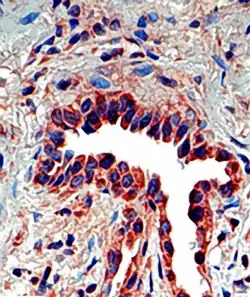

SPP1 structure corresponds to an osteopontin antibody